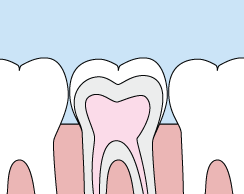

Crowns

Our crowns are a cosmetic restoration used to improve your tooth’s shape or to strengthen a tooth. Crowns are most often used for teeth that are broken, worn, or have portions destroyed by tooth decay.

A crown is a "cap" cemented onto an existing tooth that usually covers the portion of your tooth above the gum line. In effect, the crown becomes your tooth’s new outer surface. Crowns can be made of porcelain, metal, or both. Porcelain crowns are most often preferred because they mimic the translucency of natural teeth and are very strong.

Crowns or onlays (partial crowns) are needed when there is insufficient tooth strength remaining to hold a filling. Unlike fillings, which apply the restorative material directly into your mouth, a crown is fabricated away from your mouth. Your crown is created in a lab from your unique tooth impression, which allows a dental laboratory technician to examine all aspects of your bite and jaw movements. Your crown is then sculpted just for you so that your bite and jaw movements function normally once the crown is placed. Let us put some sparkle in your smile and